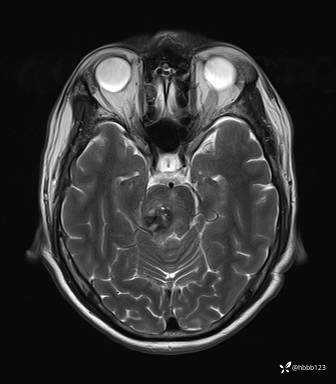

患者男,51岁。

简要病史:患者自述于1周前至某人民医院发现脑干肿瘤(具体不详),为求进一步诊断至我院就诊。

完善颅脑MRI平扫+增强,颅脑CT平扫:

T2: